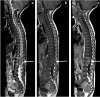

Tuberculosis (TB) remains one of the major public health threats worldwide, despite improved diagnostic and therapeutic methods. Tuberculosis is one of the main causes of infectious disease in the chest and is associated with substantial morbidity and mortality in paediatric populations, particularly in low- and middle-income countries. Due to the difficulty in obtaining microbiological confirmation of pulmonary TB in children, diagnosis often relies on a combination of clinical and radiological findings. The early diagnosis of central nervous system TB is challenging with presumptive diagnosis heavily reliant on imaging. Brain infection can present as a diffuse exudative basal leptomeningitis or as localised disease (tuberculoma, abscess, cerebritis). Spinal TB may present as radiculomyelitis, spinal tuberculoma or abscess or epidural phlegmon. Musculoskeletal manifestation accounts for 10% of extrapulmonary presentations but is easily overlooked with its insidious clinical course and non-specific imaging findings. Common musculoskeletal manifestations of TB include spondylitis, arthritis and osteomyelitis, while tenosynovitis and bursitis are less common. Abdominal TB presents with a triad of pain, fever and weight loss. Abdominal TB may occur in various forms, as tuberculous lymphadenopathy or peritoneal, gastrointestinal or visceral TB. Chest radiographs should be performed, as approximately 15% to 25% of children with abdominal TB have concomitant pulmonary infection. Urogenital TB is rare in children. This article will review the classic radiological findings in childhood TB in each of the major systems in order of clinical prevalence, namely chest, central nervous system, spine, musculoskeletal, abdomen and genitourinary system.